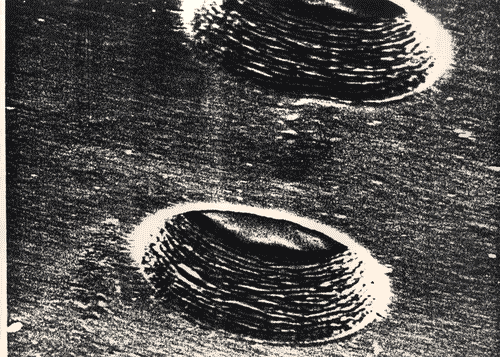

Membrana forata per la ricostruzione della pelle per la sezione Pezzi di ricambio, curata da Pasquale Alferj nella mostra tematica La natura delle cose.